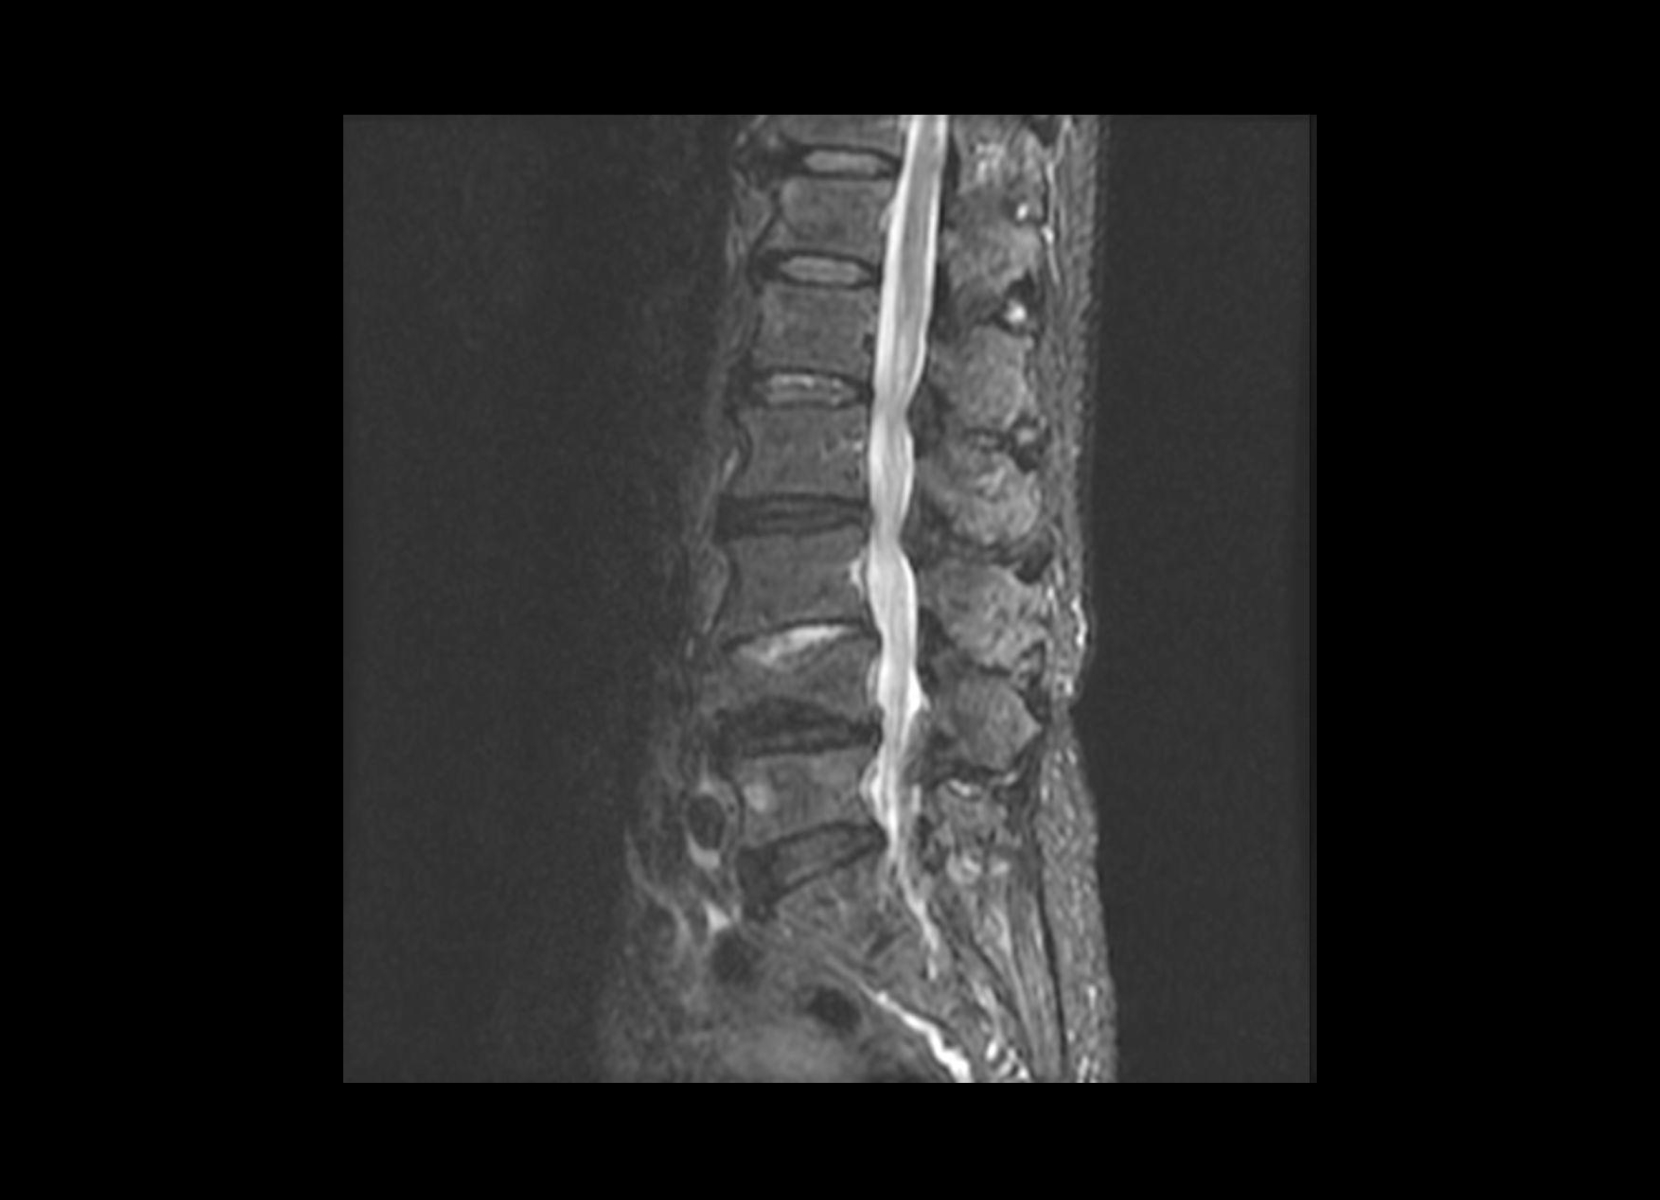

Conventional

STIR

SubtleSYNTH™

(Synthesized STIR)™

Vascular

GE 1.5T

C-spine